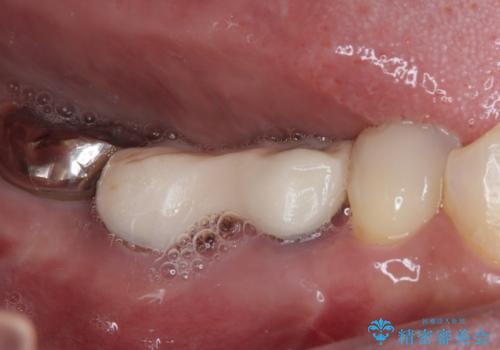

放置していたむし歯 抜歯即時埋入インプラントによる補綴治療

- むし歯を放置したままで、インプラント治療を希望して来院された患者様です。

左右ともにインプラントが必要な状態でした。

左下小臼歯は根管治療で対応する予定でしたが、診断のために歯肉を開いたところ頬側に垂直破折が認められたため、抜歯即時埋入インプラントによる補綴治療を選択することとしました。

右下は大臼歯部の歯は抜歯即時埋入インプラントにて、手前の歯は保存して補綴治療を行うこととしました。

インプラント埋入時に十分な安定値を得ることができたため、速やかに仮歯を装着し、最小限の通院回数で治療を終えることができました。